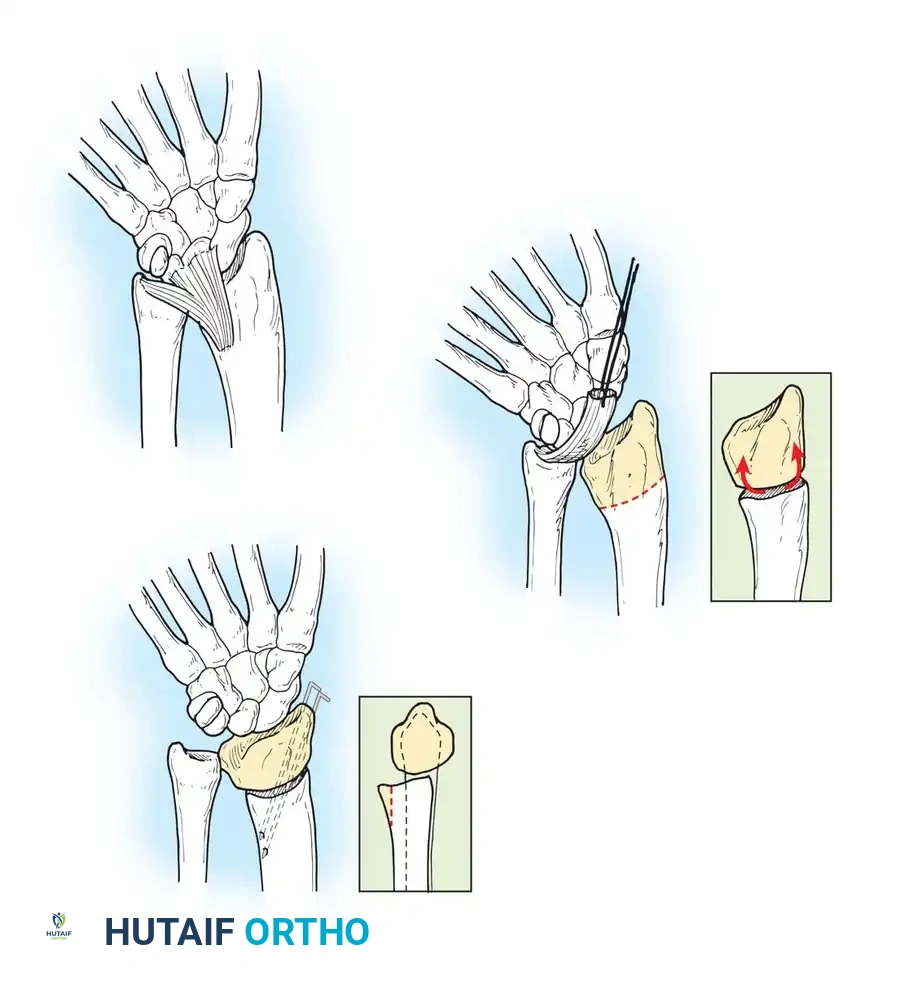

Preoperative planning diagram for a comprehensive volar release, highlighting the structures contributing to the flexion contracture.

TECHNIQUE 76-53: Comprehensive Tendon Release (Smith's Approach)

Smith emphasized a "unifying theory" of camptodactyly, advocating that all abnormal structures must be systematically addressed. The frequency of involvement includes skin (100%), FDS (66%), retinaculum cutis (55%), and lumbricals (22%).

- Incision and Skin Lengthening:

Make a volar linear incision over the affected digit and convert it to multiple Z-plasties. Ensure the central limbs of the Z-plasties are placed precisely over the flexion creases of the joints to prevent secondary scar contracture.